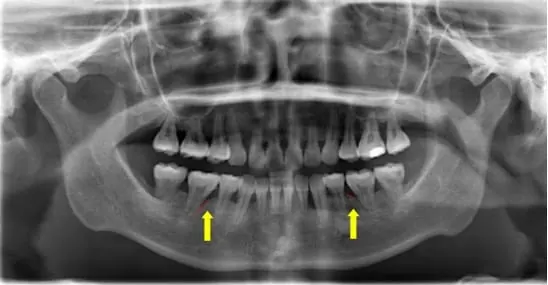

圖1: 當時第一次牙周病診斷的X光片

說明:X光片顯示牙齒齒槽骨侵蝕,患者齒槽骨已遭中度至重度侵蝕。(如箭頭所示)。